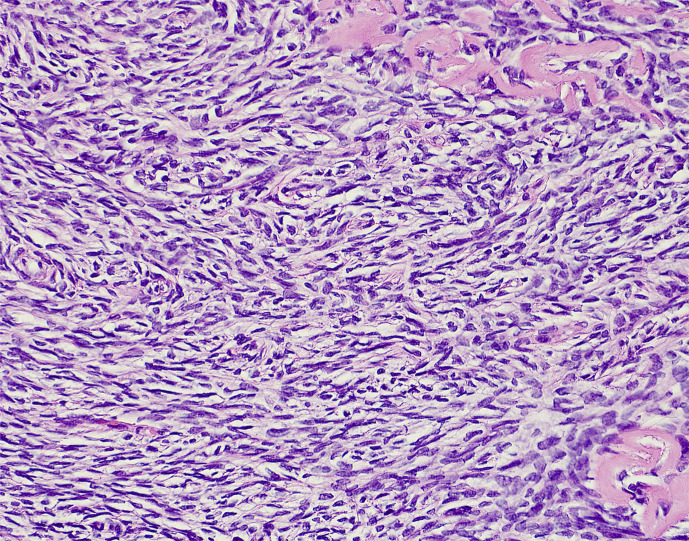

Case presentation: We present the case of a 47-year-old female with high-risk early-stage hormone receptor-positive breast cancer who despite use of GnRH agonists did not achieve an estradiol level within the postmenopausal range. She had received two different GnRH agonists (leuprolide and goserelin) and later underwent a bilateral salpingo-oophorectomy (BSO). The pathology showed stromal hyperplasia in both ovaries. After the BSO in April 2024, the GnRH agonist was stopped. The serum estradiol level remained elevated (not in the postmenopausal range) after surgery for 12 months, prior to decreasing to the postmenopausal range.

Abstract Image